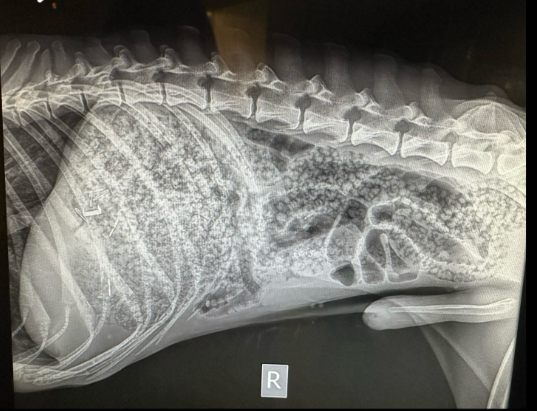

In another video, the woman posted the dog's X-ray scans, which showed the water beads inside its digestive tract.

The canine was only able to pass about a quarter of the beads it had swallowed, which had not yet been hydrated.

The remaining beads had to be removed via surgery, the vet tech explained.